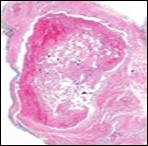

On microscopy, superficial squamous epithelial surface is intact. Sub-epithelial connective tissue stroma exhibits slit-like, vascular spaces. Upon extended magnification, multiple, intravascular papillary projections encompassed within a hyalinised stroma are discerned. Centroidal calcification appears in combination with intravascular, papillary endothelial cell proliferation, lined with singular layer of endothelial cells devoid of cytological atypia6, 7.

Characteristically, the vascular neoplasm denominates numerous papillae within blood vessels. Papillae are coated with singular or dual layer of flattened endothelial cells with an encompassing hyalinised, fibrous tissue core. Vascular lumen is distended with thrombosis. Foci of haemorrhage with fibrinous and purulent exudate are discerned. Tumour perimeter depicts inflammatory granulation tissue. Cholesterol clefts and focal reactive bone formation may concur. Extraneous squamous epithelium may be discontinuous and ulcerated. The neoplasm is devoid of features of malignancy4, 6.

Numerous micro-calcifications can be observed within the lesion which may engender vascular occlusion and tissue necrosis6. Figure 1, Figure 2, Figure 3, Figure 4, Figure 5, Figure 6, Figure 7, Figure 8.

Figure 2 Papillary endothelial hyperplasia delineating papillary articulations with an endothelial cell layer, thrombotic exudate and fibrinous debri (1.